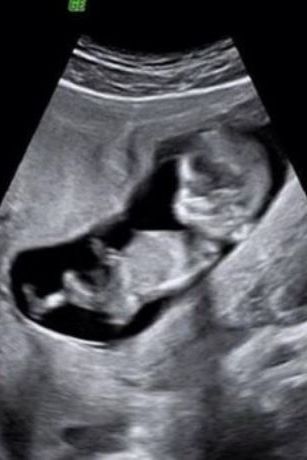

Πασίγνωστη Ελληνίδα ηθοποιός περιμένει το δεύτερο παιδί της & δείχνει το υπερηχογράφημα

Πολλές είναι οι γυναίκες της σόου μπιζ, τελευταία, που μοιράζονται την πιο όμορφη στιγμή της ζωής τους, στα social media με τους διαδικτυακούς τους φίλους...